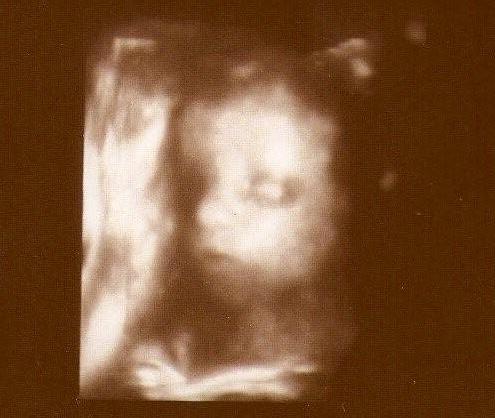

" U nas bez zmian. Nakaz leżenia obowiązuje i tak chyba będzie do końca(...) Dziękujemy z Mają za wszystkie życzonka od Kochanych dziewczyn z bbi przesyłamy wzajemnie. Buziaczki"